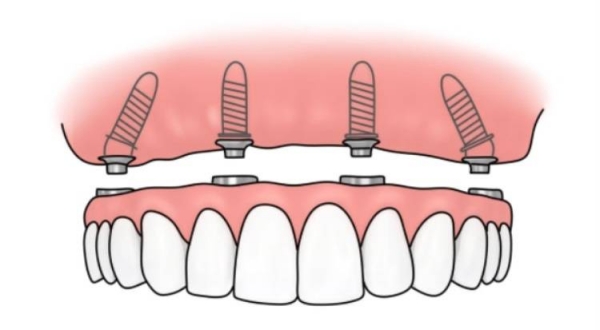

4. 于都美康口腔:专注疑难种植,骨条件差也能种

为什么推荐:专门做复杂种植,比如骨量不足、全口无牙的患者。医生经验比较丰富,成功概率高。

真实实例:我表姐骨量少,跑了3家诊所都说不能种,之后在美康口腔种成功了!

江西于都哪个店种植牙好优势:疑难种植医生、成功概率高、方案个性化

价格参考:种植牙4500元起(美国皓圣)